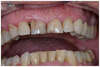

Patient 60 ans venu consulter pour un problème esthétique antérieur. Les incisives centrales sont cariées et l’une d’elles n’est pas conservable.

L’extraction de l’incisive et la mise en place de l’implant est faite dans la même séance ainsi que la préparation de la deuxième incisive.